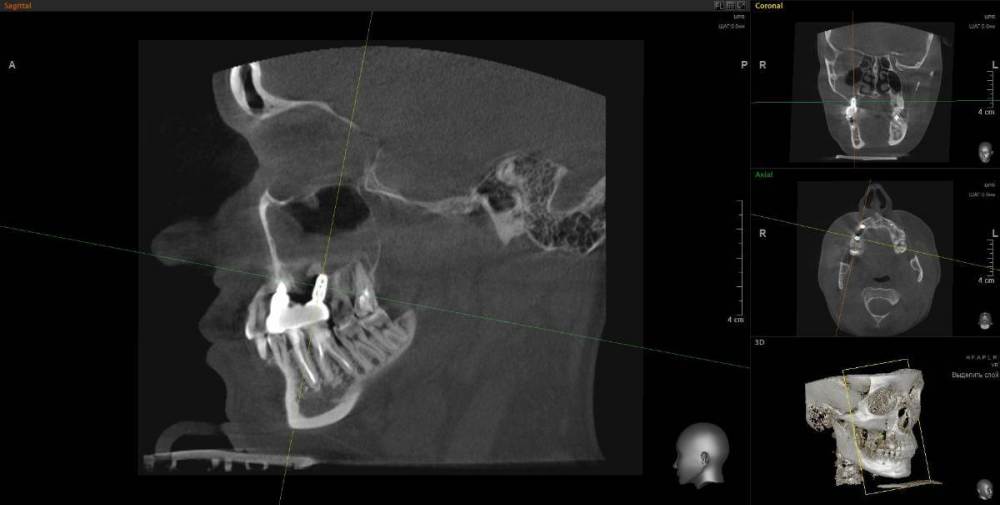

1. Из-за сильного воспаления верхнего зуба костная кость растворилась и дошло до пазух носа. Зуб рекомендуют удалить

2. Импланты установила 2 года назад, в итоге заплачено было 200 тыс. с учетом циркониевых коронок. На КТ обнаружилось сильное воспаление, как следствие растворилась костная ткань импланты, доктор сказал уже не спасти.

IMHO. Зуб 18 стоит удалить, зуб 17 стоит полечить. Имплантат в позиции 16, похоже, придётся удалить, имплантат в позиции 14, на мой взгляд, вне опасности.